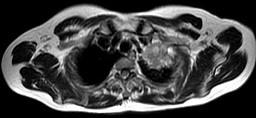

问题 男,68岁,声音嘶哑半个月,行MRI检查如图,其最可能的诊断为 ( )

选项 A.右上肺癌 B.左上肺结核球 C.左上肺炎性假瘤 D.左上肺癌 E.左上肺动静脉瘤

答案 D